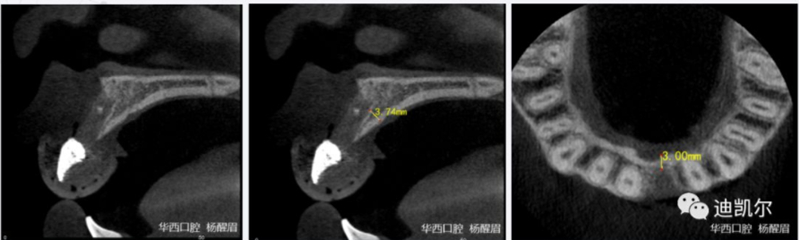

術(shù)前CBCT圖像和測量數(shù)據(jù)

*CBCT顯示骨缺損嚴重,種植窩洞制備困難,種植體很難獲得初期穩(wěn)定性